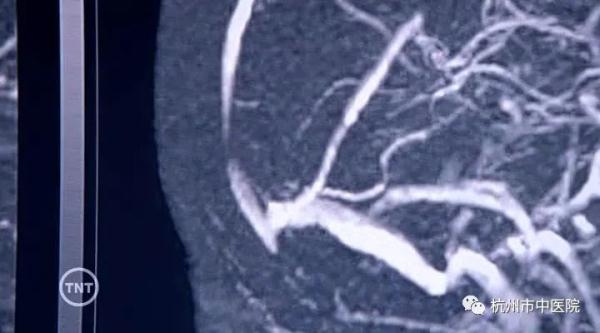

患者有口服避孕药病史,加上凝血功能D-二聚体水平偏高,再结合磁共振检查结果,方芳主任考虑患者可能是颅内静脉窦血栓形成,随后立马给她安排了颅脑磁共振静脉血管成像MRV检查,果不其然在患者脑部发现了窦汇、左侧横窦及乙状窦栓塞(血栓),也就是颅内静脉窦血栓。神经内科医生给邵女士进行了低分子肝素及华法林抗凝治疗,经治疗后患者好转出院。